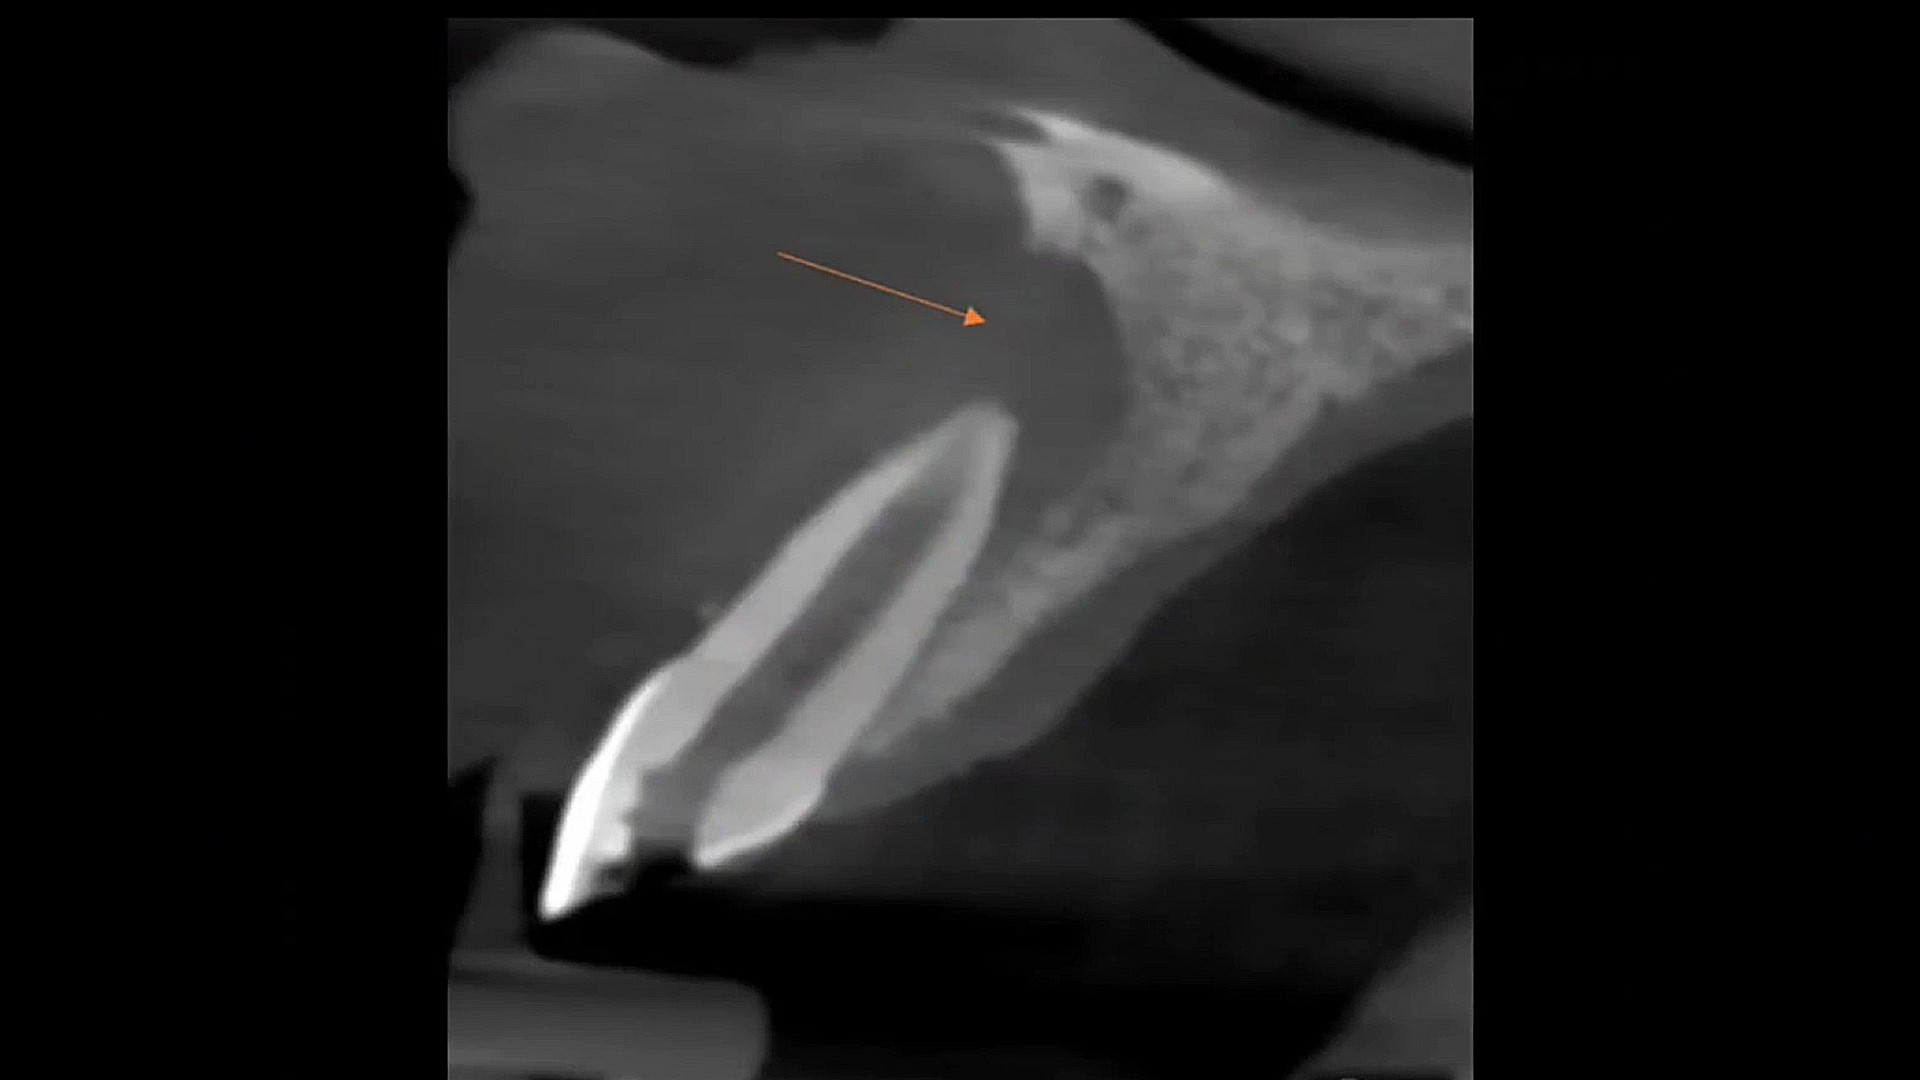

HOW TO MANAGE LARGE PERIAPICAL LESION WITH NON-SURGICAL ENDODONTIC TREATMENT